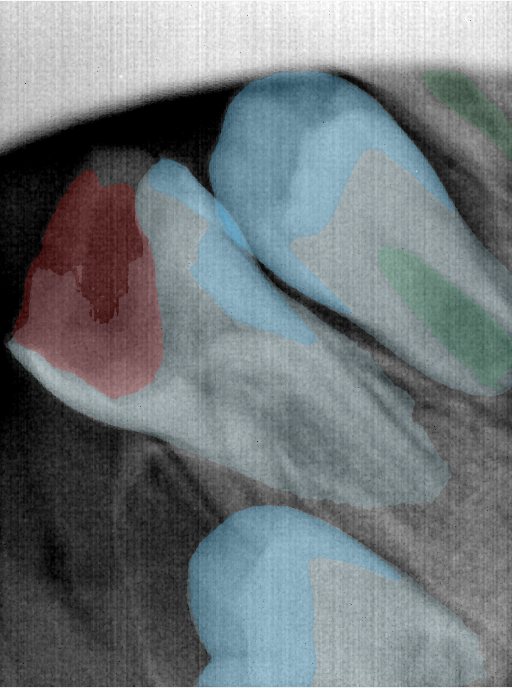

CR/DR 牙齿分割阶段记录

当前进展

- 完成了 CR/DR 牙齿相关分割训练

- 当前结果已经达到阶段预期,但仍有细节问题需要继续处理

相关测试

遇到的问题

- 训练过程中出现过 mask 下移问题

- 部分结果会出现 box 填充异常

- mask 边缘仍然有比较明显的锯齿感

参考

第二版算法问题测试